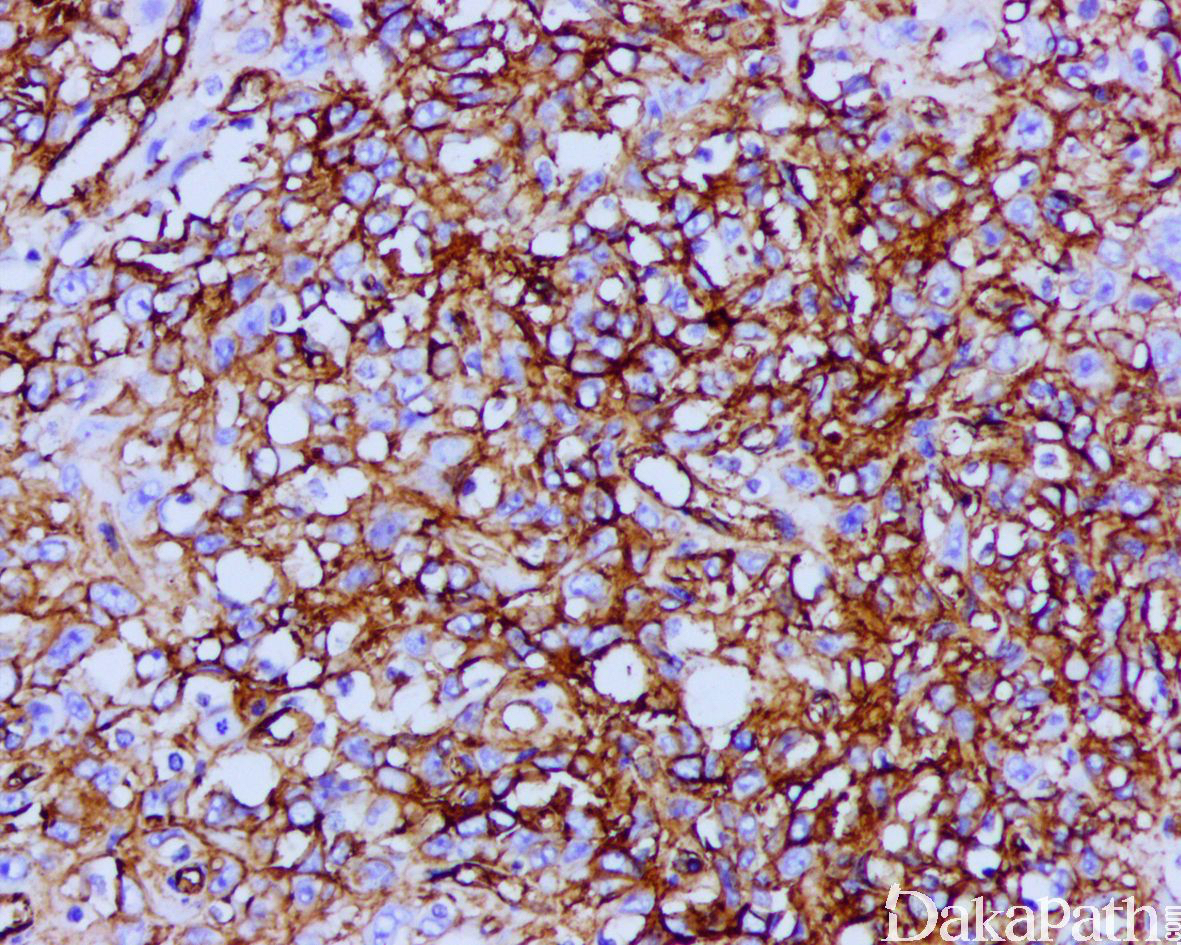

免疫组织化学染色:

瘤细胞 AE1/AE3. EMA、CK8. CK19 和 vimentin 常阳性,50%-70%病例 CD34 阳性,95%以上显示 SMARCB1(INI1)表达丢失;部分病例可表达 MSA、α-SMA、S-100. ERG 和 NSE,偶尔表达 SALL4,—般不表达 CK20. desmin、NF、CEA 和 CD31。